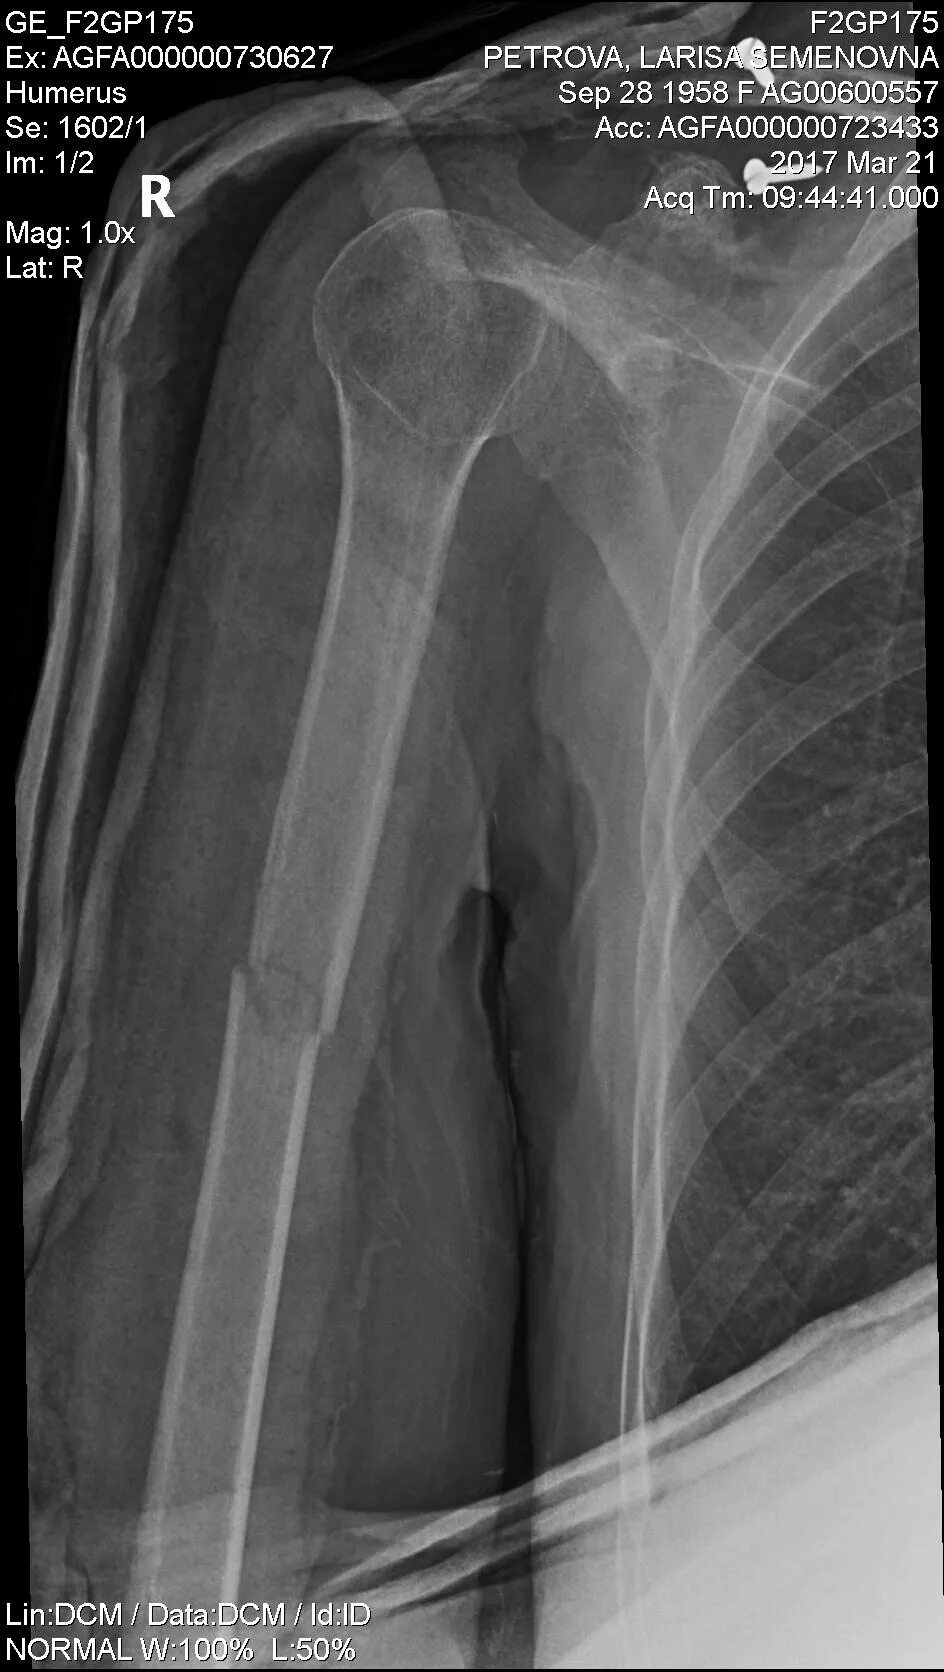

Сколько срастается плечевой перелом